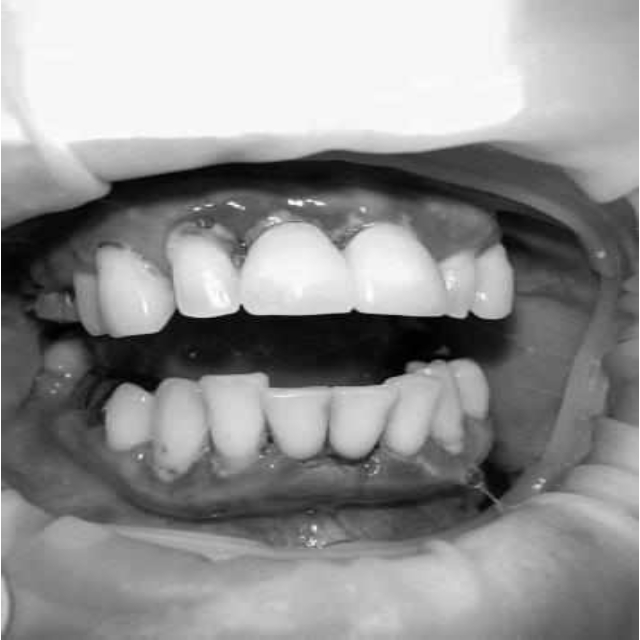

Ранее у пародонтолога не наблюдалась. При осмотре выявлены: неудовлетворительная индивидуальная гигиена полости рта, пародонтальные карманы до 7 мм, обильная кровоточивость и гноетечение из пародонтальных карманов, подвижность зубов 4.2, 4.1, 3.1, 3.2 II степени, обильные над- и поддесневые зубные отложения (рис. 1). На ортопантомограме отмечается резорбция костной ткани до ½ длины корня, очаги остеопороза (рис. 2). Пациенту был поставлен диагноз хронический генерализованный пародонтит тяжелой степени тяжести. При осмотре была составлена пародонтограмма с использованием компьютерного зондирования (рис. 3).

Рис. 2. Ортопантомограмма исходной ситуации пациента состояния полости рта